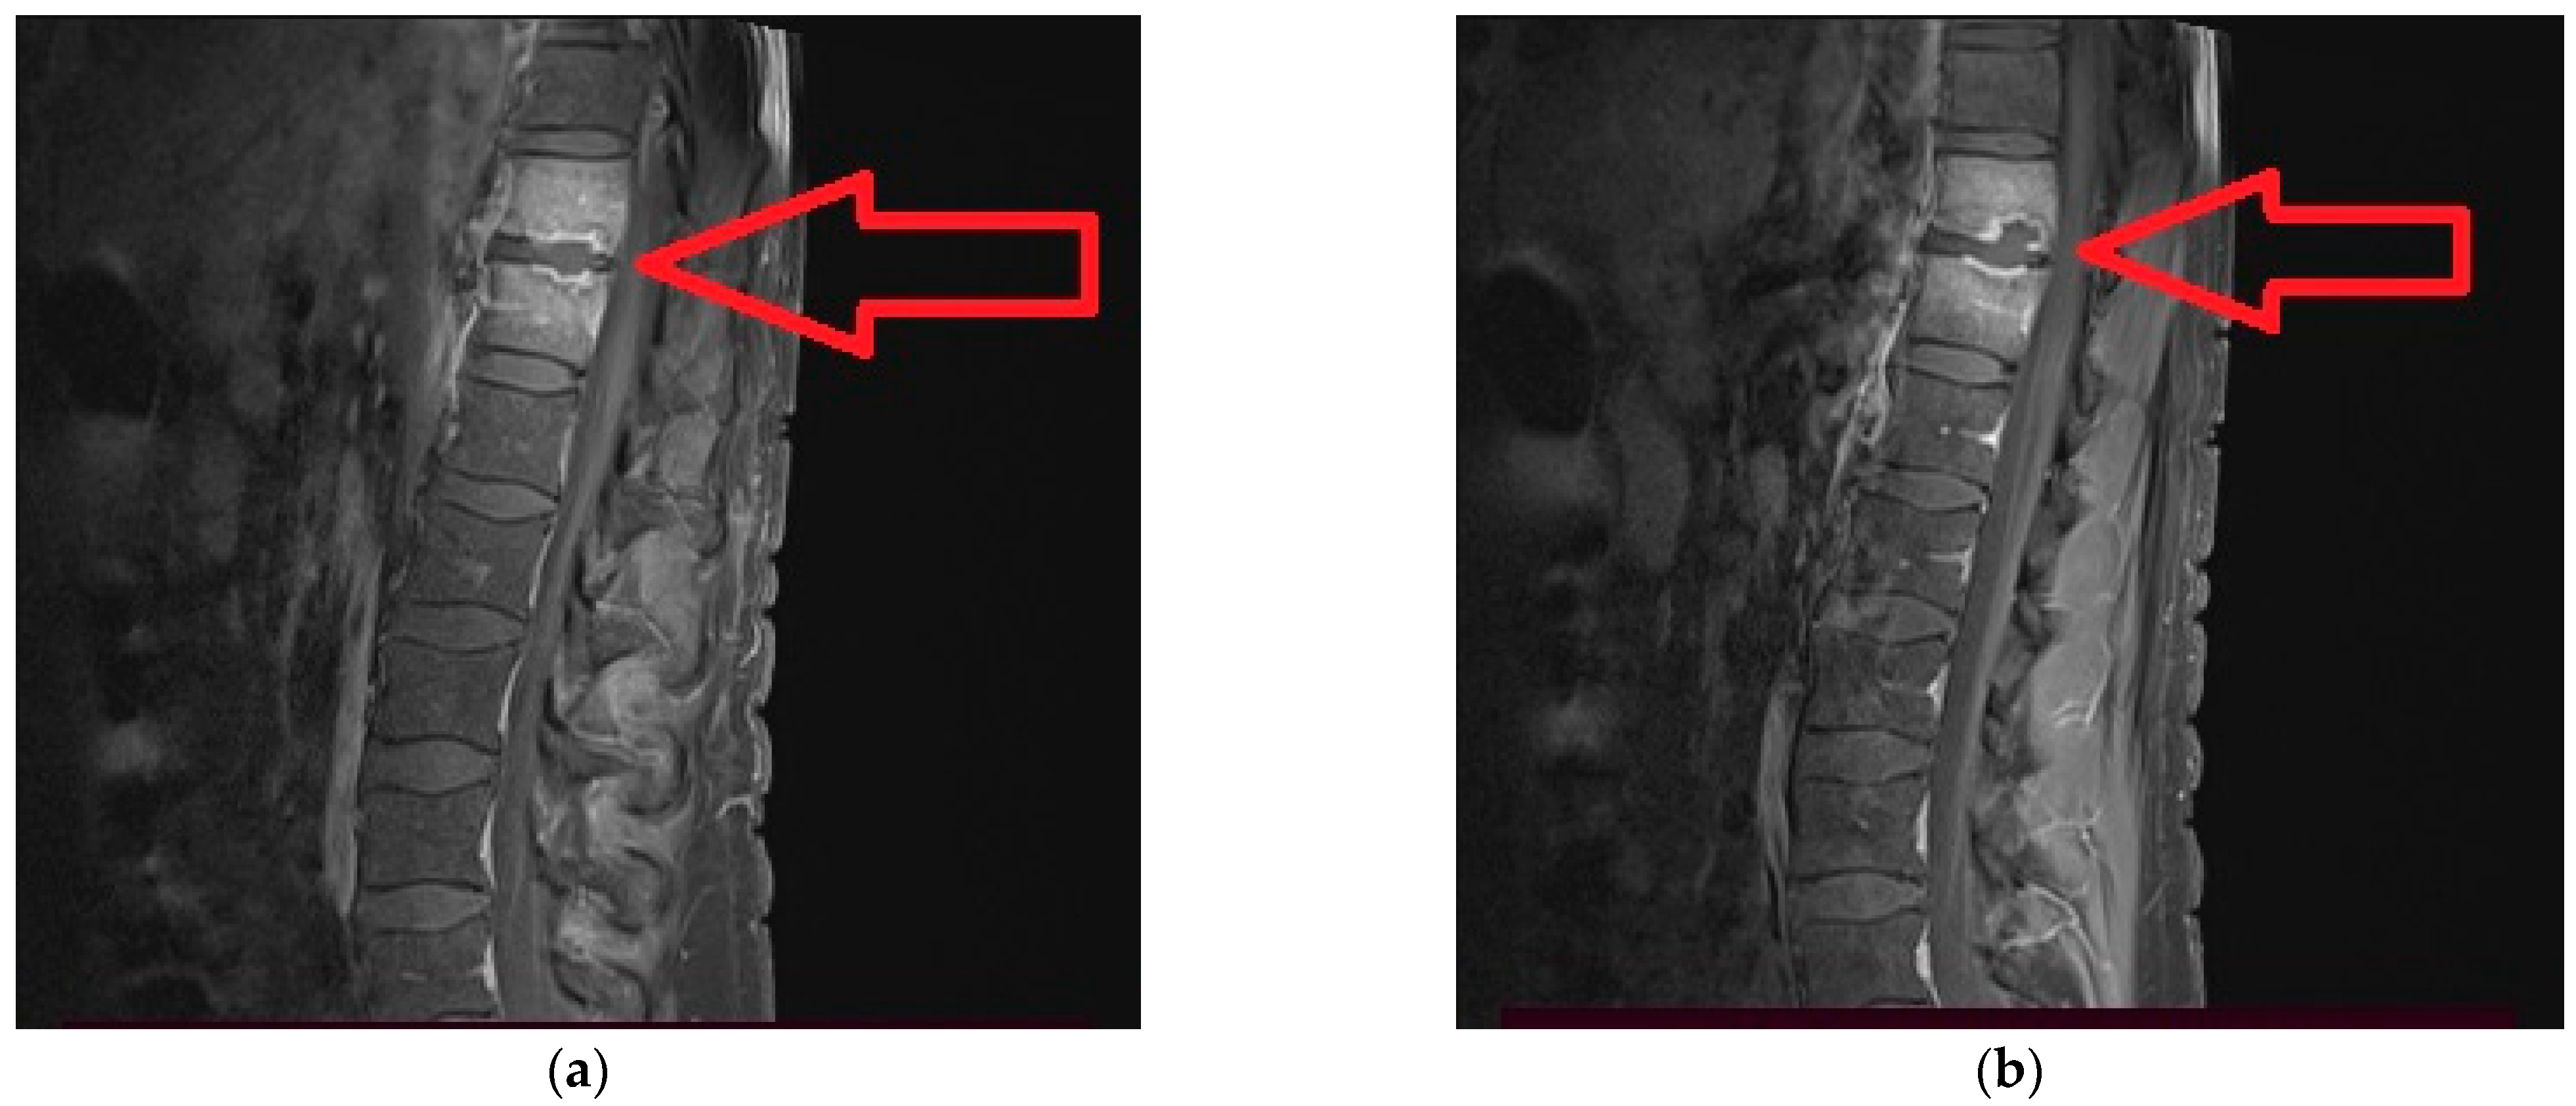

2. Case Report